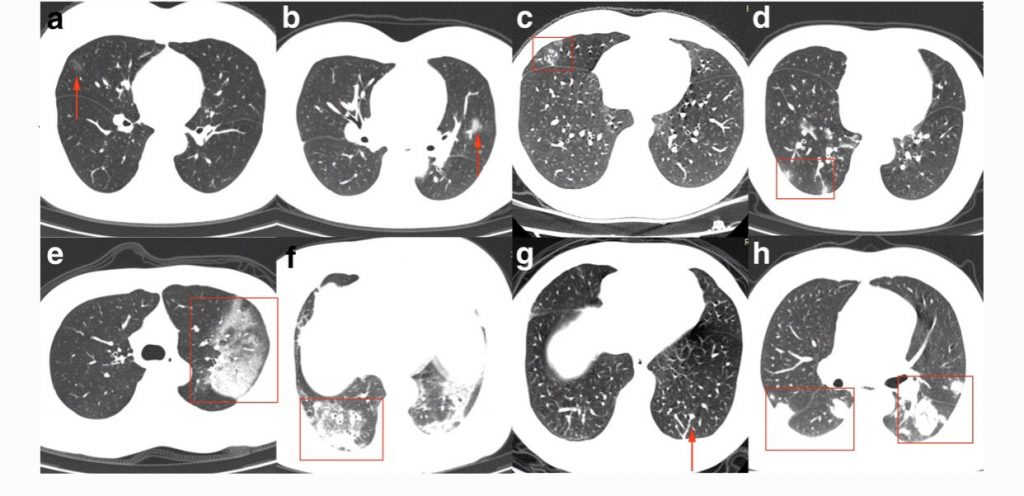

De beelden van de foto’s wisselen, maar in het algemeen ziet men in verschillende longgebieden ontsteking, zoals hier: pic.twitter.com/PeGH8caDbI

— Sander de Hosson (@shossontwits) March 1, 2020

De witte gebieden met pijltjes zijn de gebieden van de longontsteking, die op deze foto zwart horen te zijn. U ziet uiteraard ook de bronchieën en de bloedvaten.

De Koreanen publiceren veel studies.

We krijgen een steeds duidelijker beeld van de verschillende afwijkingen op de foto.

Voor de liefhebber: https://t.co/kFPzWdYzKU pic.twitter.com/bBrav2vUJo— Sander de Hosson (@shossontwits) March 1, 2020